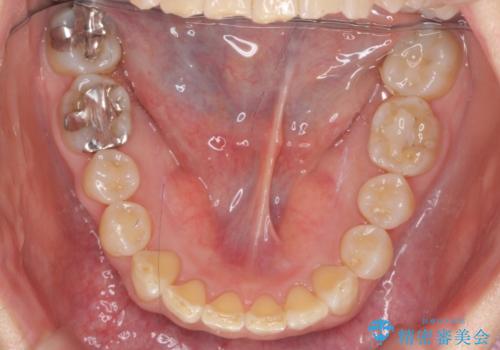

50代女性 インビザライン かみ合わせが深く、難しい症例

かみ合わせが深く、上の歯が咬みこんで下の歯にワイヤーがつけられない状態で、ワイヤー矯正はかなり難しい状態でした。

反対咬合や、すれ違い咬合もあり、大変難しいケースでしたが治療することができました。

かみ合わせが深い方はもともとかみしめが強く、マウスピース矯正を長期にすると、奥歯が咬まなくなってくる症状が強くなります。

今回もそういった状態になったのを、装着時間や歯の移動を工夫する形で治療しました。